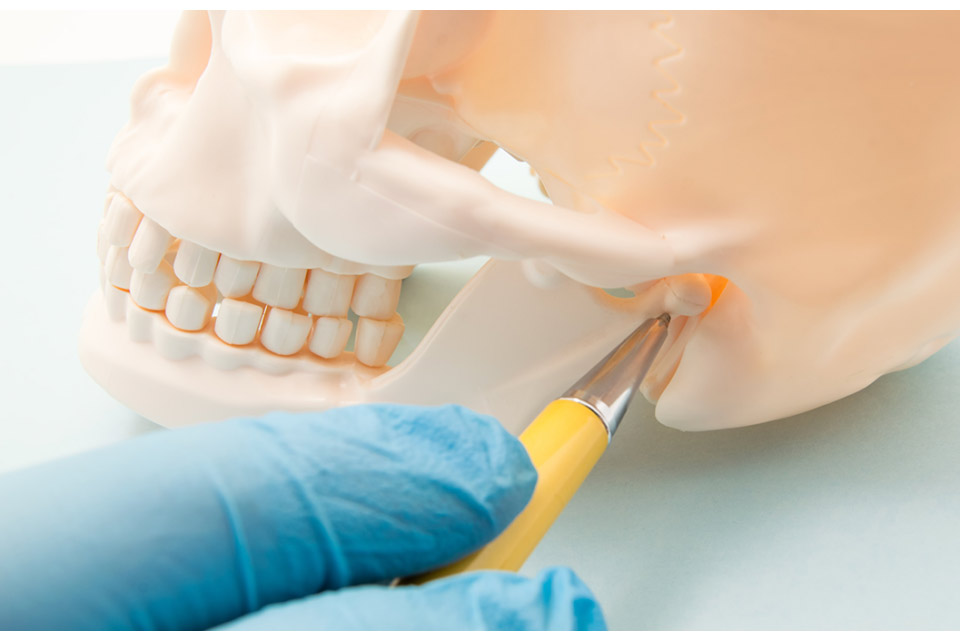

Orthognathic & Maxillofacial Surgery

At SolSide Dental Clinic, our specialists perform precise orthognathic and maxillofacial surgeries to correct jaw misalignments, improve chewing function, and enhance facial aesthetics. With advanced digital planning and 3D imaging, we ensure accuracy, safety, and predictable results.